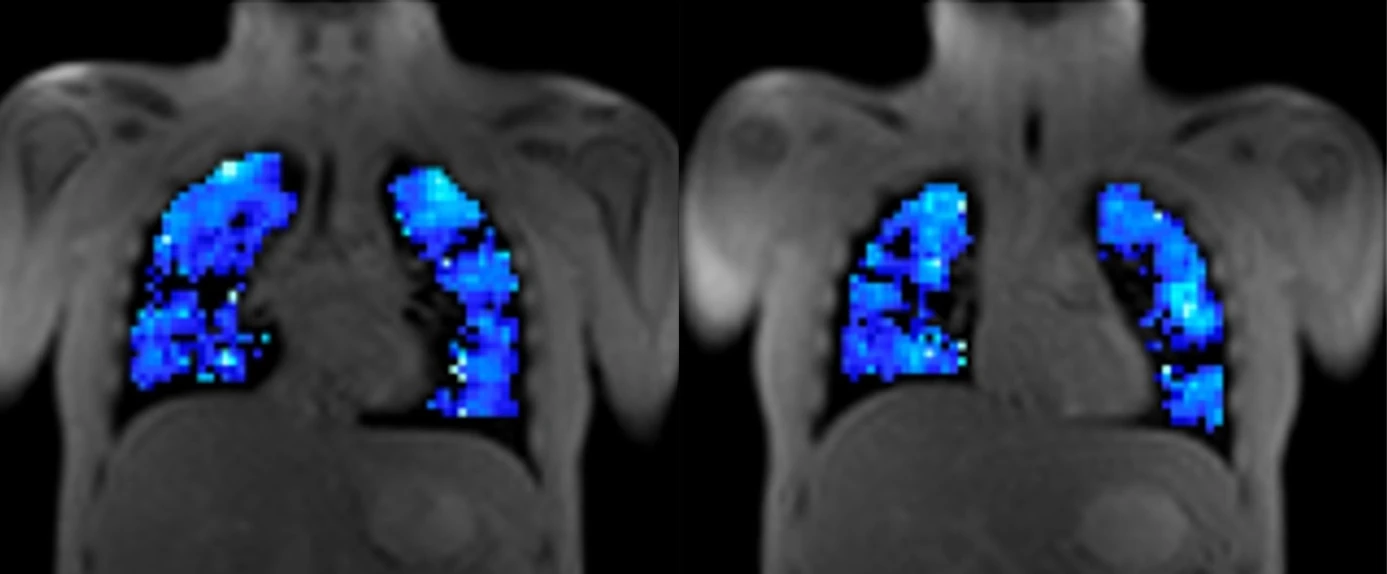

Respiratory

Quantitative MRI and ventilation imaging to support respiratory drug development.

- Oxygen-enhanced MRI (OE-MRI) ventilation biomarkers

- DCE-MRI perfusion and microvascular measures

- Motion-based ventilation imaging without gases

- Support for hyperpolarised 129Xe studies

- Validated methods across vendors and sites